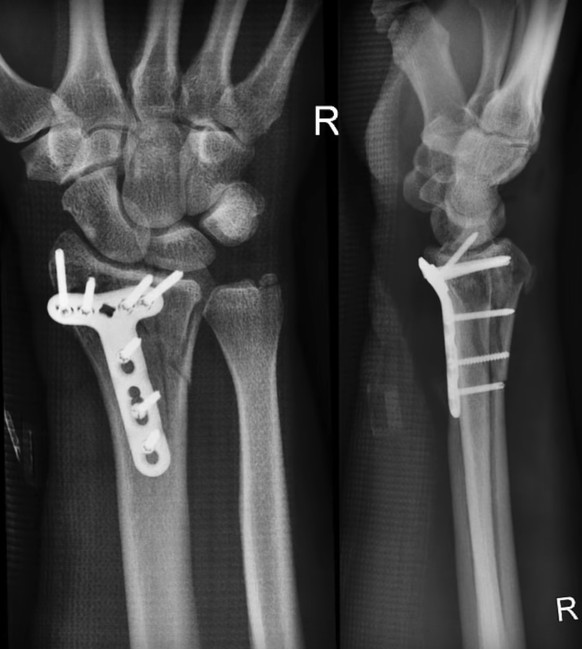

Bei der Landung kam Gursky einigermassen glimpflich davon: Er zog sich einen Bruch am rechten Handgelenk zu, dieser musste mit einer Titanplatte und sieben Schrauben gesichert werden. Zudem riss er sich eine Sehne im linken Bizeps. Der Amerikaner wurde im Spital operiert und konnte es am nächsten Nachmittag wieder verlassen.